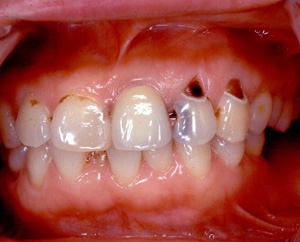

術前口腔内(正面観)